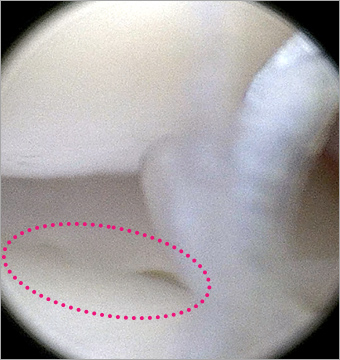

단열된 십자인대

단열된 십자인대

정상 반월판의 물결 모양

(Oyster flounce)

본원 시술 사진